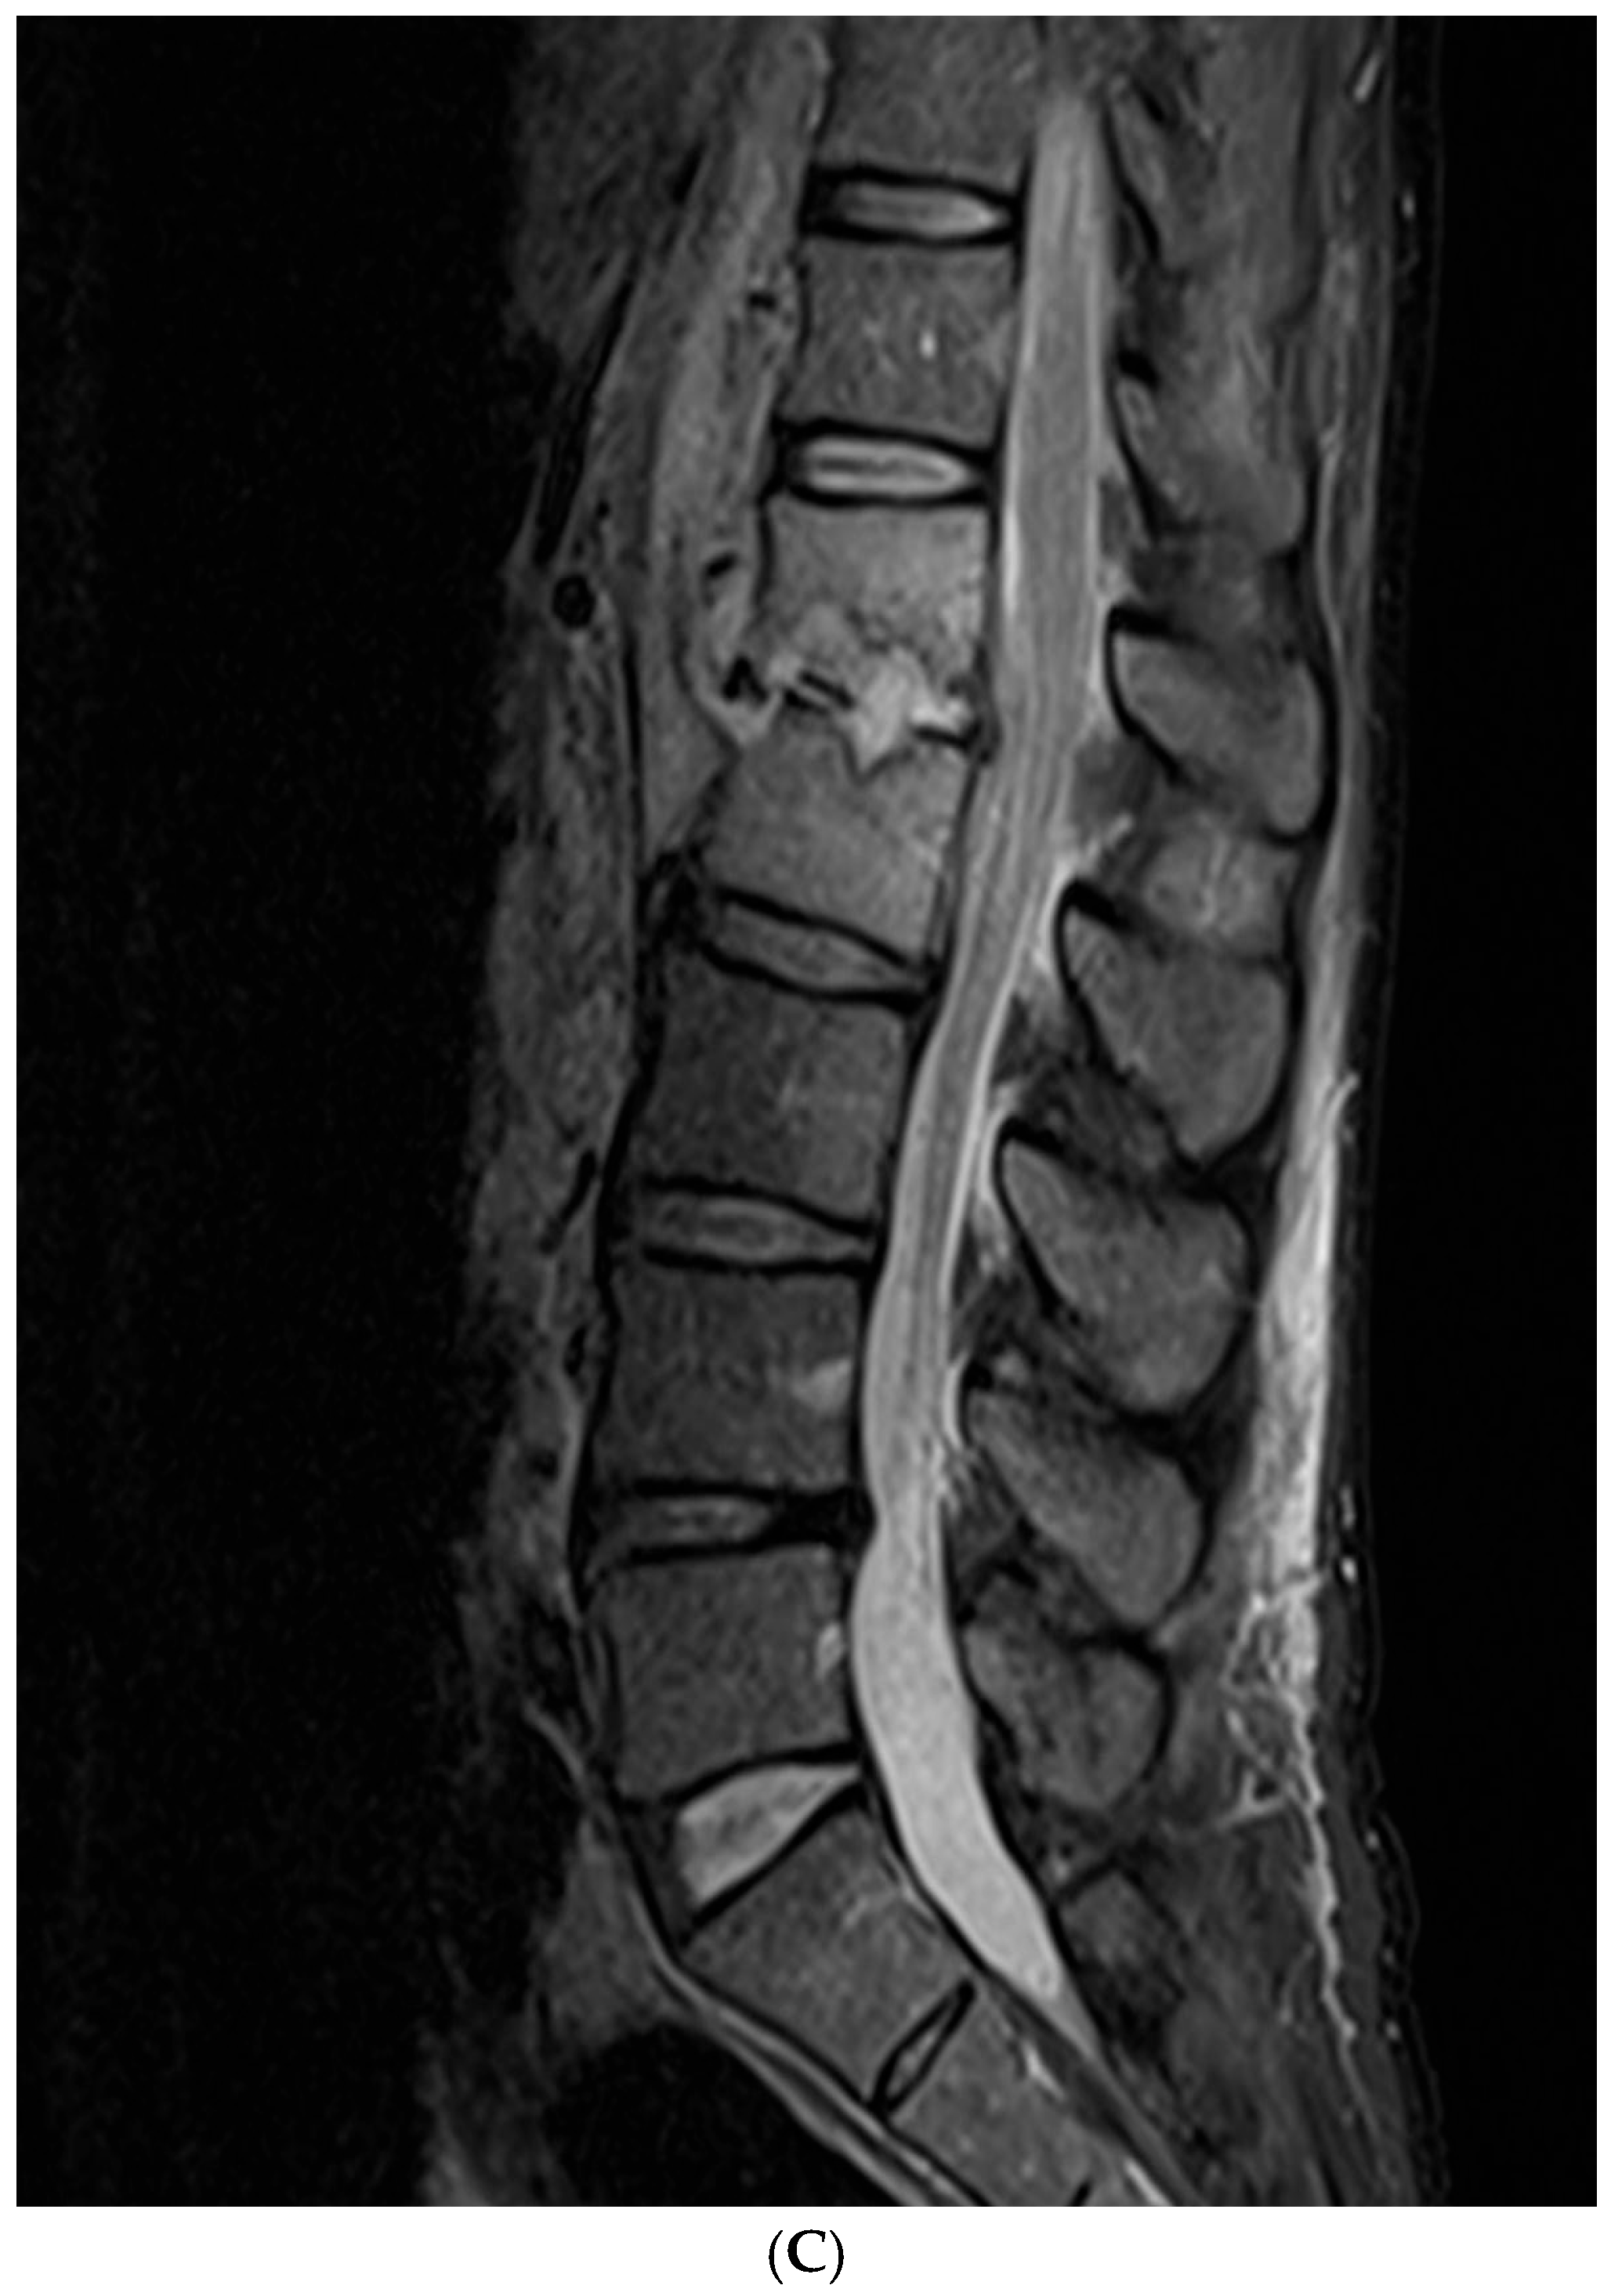

2.2. Imaging Scoring Systems

3.2. Analyses of Imaging Findings

4.2. Imaging Findings